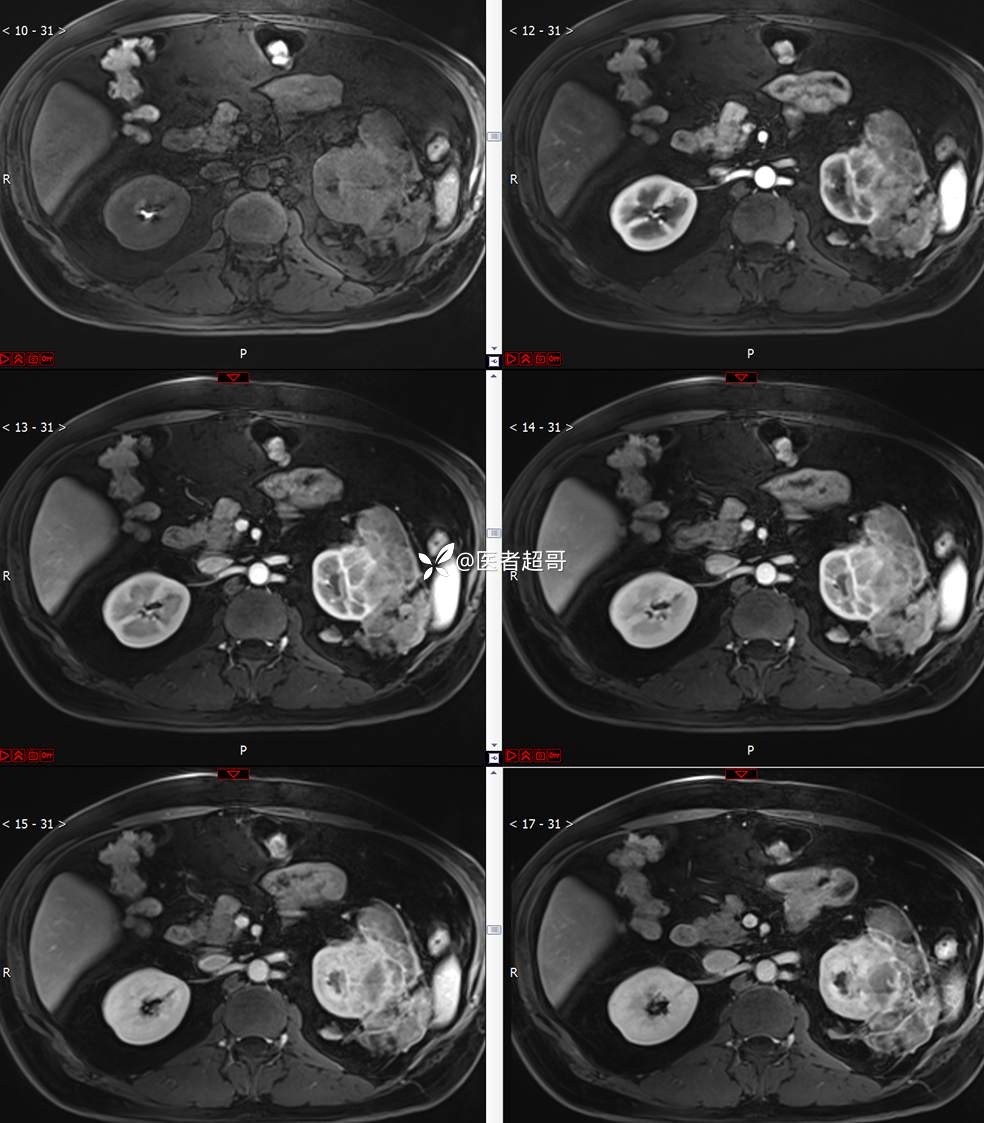

主 诉:查体发现左肾肿物9天。

现病史:患者9天前于附属医院行常规腹部CT检查时,发现左肾占位性病变并肾周脂间隙软组织增多,自述无明显腰腹部不适,无尿频、尿急、尿痛及肉眼血尿,未予特殊治疗,患者近期无头晕头迷,胸闷气急,腹胀腹泻及其他部位明显不适,遂至我院就诊,门诊以“肾肿物”收入院,患者自发病以来,精神可,睡眠饮食可,大便正常,体重无明显减轻。